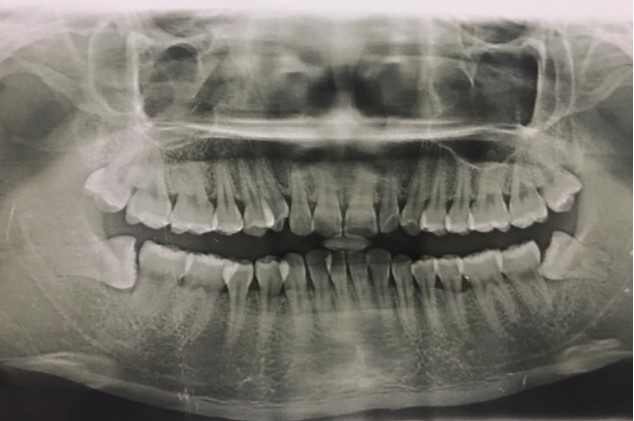

患者,男,38歲。上前牙變色1年,自述上前牙5年前受過外傷,唇側(cè)傾斜,檢查可見左上1牙冠變色,牙冠缺損近1/2,牙髓測試無反應(yīng),X線根尖片顯示患牙無明顯異常,全景片顯示雙側(cè)下頜智齒近中阻生,之前有發(fā)炎化膿病史,目前無咀嚼不適??谇黄溆酂o異常。

檢查情況及X線片見下圖:

病例分析1

(2)檢查見左上1牙冠變色,牙髓測試無反應(yīng),牙冠缺損近1/2,X線片無明顯異常。

非主訴疾病的診斷依據(jù):X線全景片顯示雙側(cè)下頜智齒近中阻生。